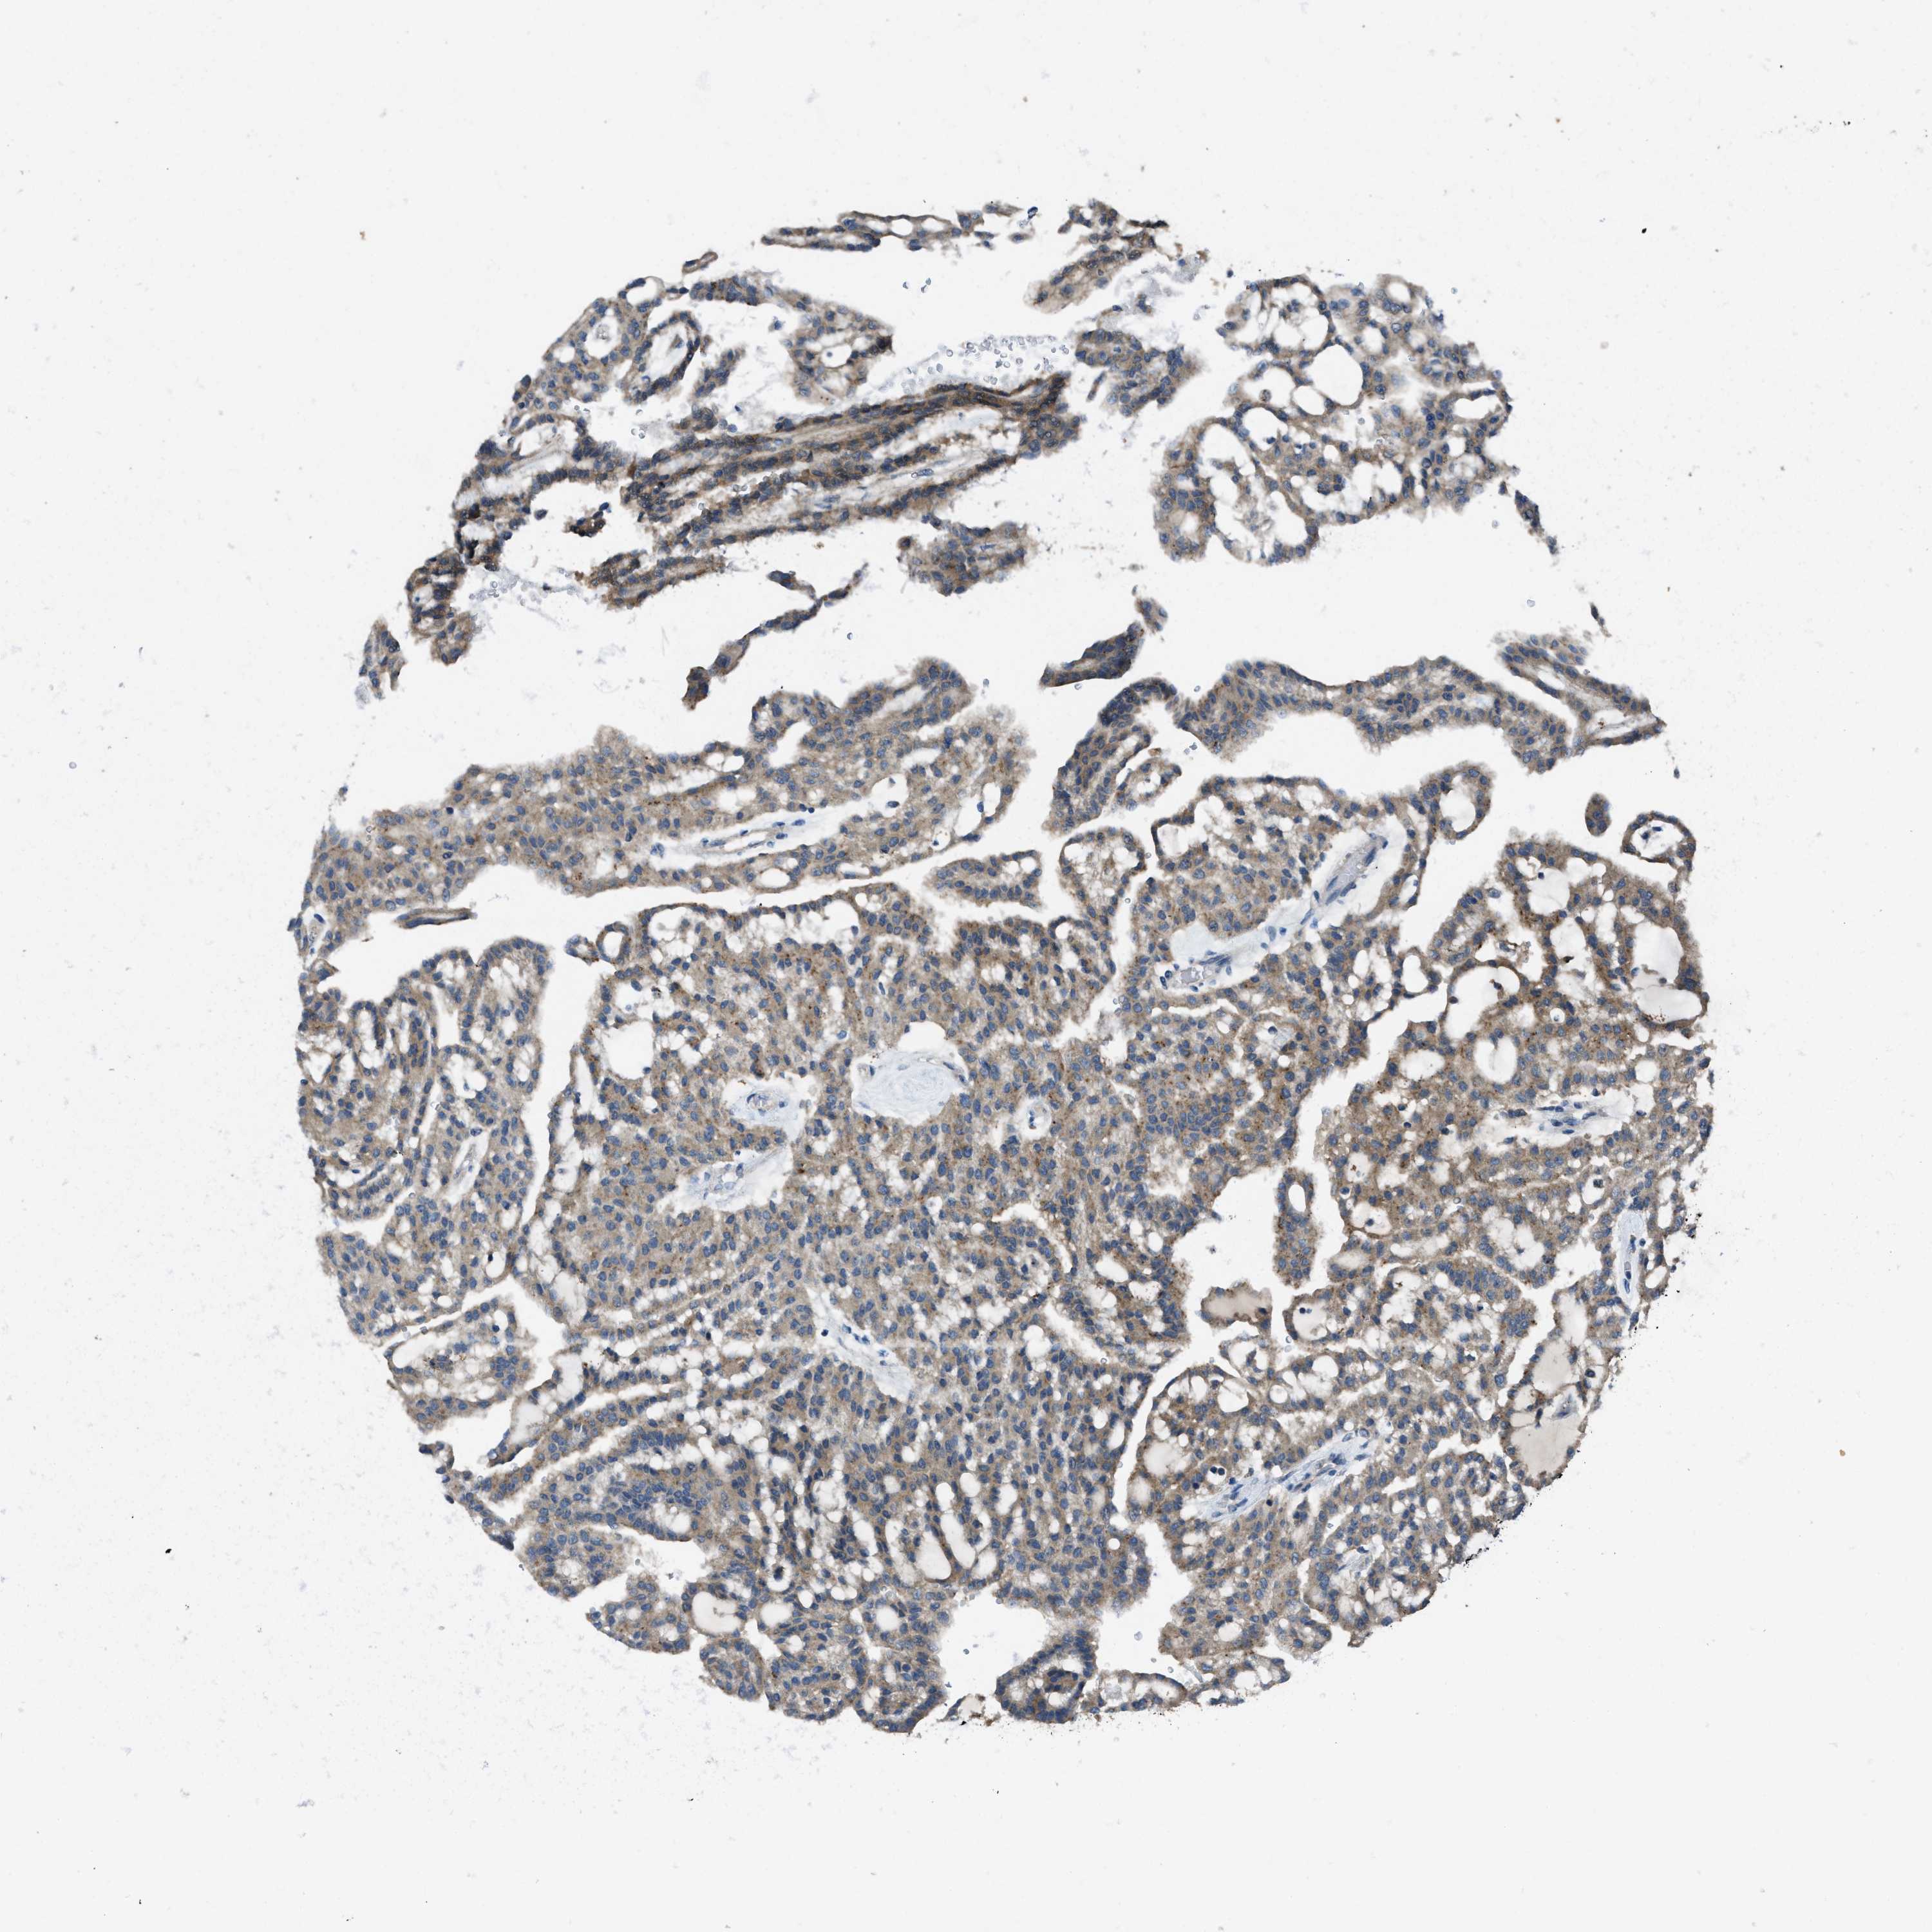

MAP3K20